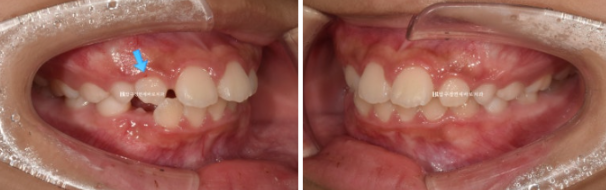

23.10

보호자가 보기에 가장 고치고 싶은 것은 돌출이고 앞니 사이즈가 큰 편 입니다.

파란 화살표 측절치 치아는 아래와 거꾸로 물리는 반대교합입니다.

윗니 뻗침 즉 돌출 때문에 입술이 잘 안 다물어지는 입술부전증의 결과로 턱끝 근육이 울퉁불퉁하게 주름이 잡히는 호두턱 호두주름도 있습니다.

치아 나올 공간이 부족한 것은 아니여도 소량의 악궁확장을 통해 앞니 돌출을 어느정도 해소하기로 했습니다.

입술부전증이나 돌출을 완전히 해소하려면 나중에 발치교정이 필요할 수도 있지만 보호자가 비발치 치료를 원했습니다.

무턱 주걱턱 비대칭 등의 골격적 문제는 없었어서 바로 인비절라인 퍼스트 치료에 들어갔고 첫 장치를 끼기 시작한것은 23년 11월입니다.